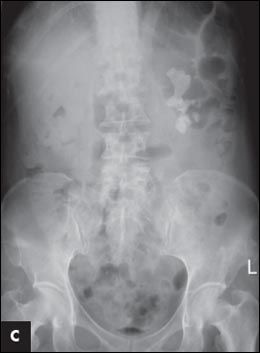

) and after the second PCNL (

C

). Complete stone clearance is achieved after the third PCNL (

The patient underwent transurethral incision of the right ureterocele and ureteroscopic removal of the ureteral stone. Simultaneous right percutaneous nephrolithotomy (PCNL) was performed, and a ureteral stent was inserted at the end of the procedure (Figure 1B). Second stage right PCNL for the residual stones was performed 2 weeks later, and all the stones were cleared (Figure 1C). Left PCNL was also performed with clearance of all the residual stones (Figure 1D). Stone analysis revealed that the calculi were composed of 76% magnesium ammonium phosphate (struvite) and 24% calcium carbonate apatite.